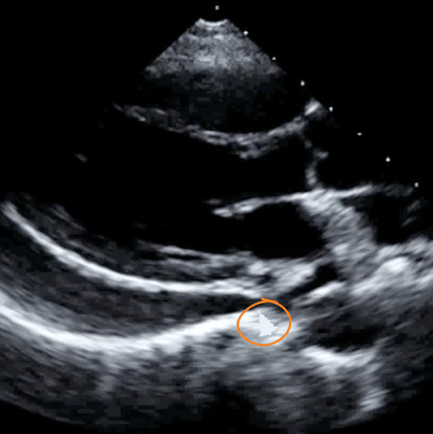

🧠 Challenge Case of the Month: Kidney & Bladder

Case History: This 90-year-old patient presents with hypotension, vomiting, and severe abdominal pain.

Please evaluate his abdomen with ultrasound.👇

Findings: Large heterogeneous and vascular gastric mass measuring 12 cm in greatest dimension without evidence of gastric perforation or bleeding, confirmed by CT to be a gastrointestinal stromal tumor (GIST)